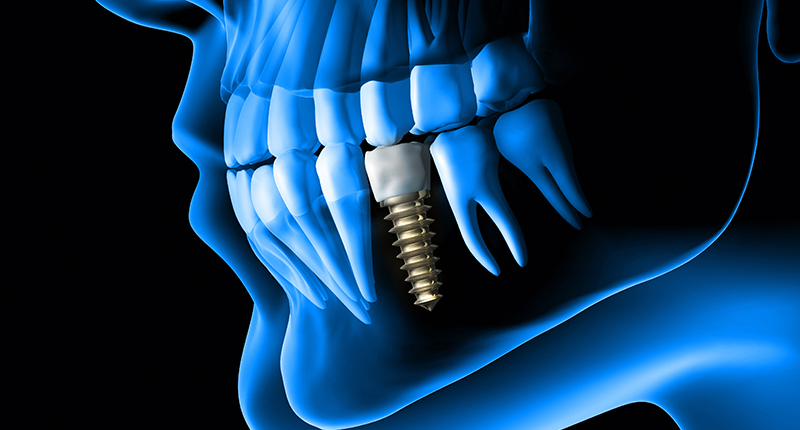

임플란트는 다양한 이유로 치아를 상실했을때 자연치아를 대체해주는 치료입니다.

인체에 무해한 티타늄으로 만들어진 인공치근을 치조골에 식립한 후 치아 모양의 보철물을 씌워 올리는

치료방법으로 자연치를 대체해주는 다른 방법인 틀니나 브릿지에 비해 기능적,심미적으로 우수합니다.

02 임플란트 구조

임플란트는 보철, 지대주, 인공치근으로 구성되어 있습니다.

[보철]

인공으로 만든 치아 모양의 크라운을 씌워 치아 외측 상부를 완성해줍니다.

[지대주]

크라운과 임플ㄹ나트 사이를 지대주와 스크류로 연결시킵니다.

[인공치근]

치조골에 심어져 치아의 뿌리 역할을 합니다.